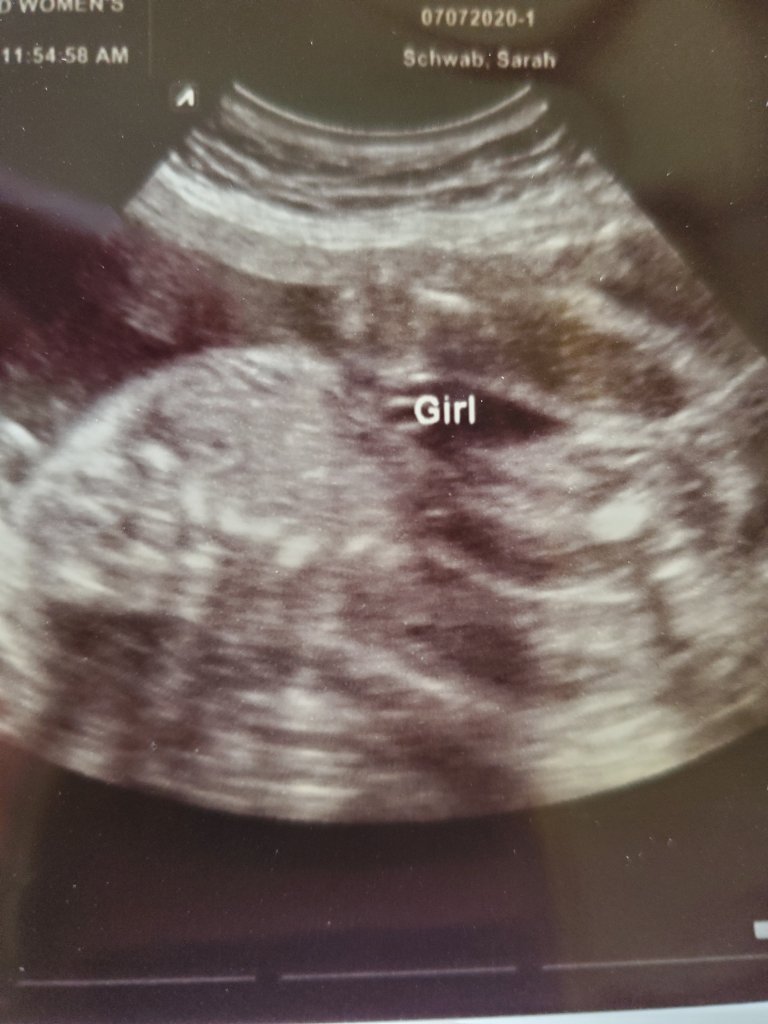

So, yesterday, we got to have an ultrasound. I really just wanted to see baby, and make sure there was only one! You don’t even know how many people told us we were having twins this time around! My midwife got to come along and see baby too and positioning.

The very first thing we see is a little rump with legs tightly closed! Of course! The ultrasound tech decided she would do some measurements and then see if she could tell boy or girl.

After a few attempts we got a good view! We were all so excited!

It’s

A

GIRL!